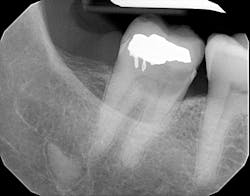

Taking care of the patient’s chief complaint was one thing, but what really caught my eye was an 8 mm x 8 mm purple/dark blue raised nodule on the right side of the vermilion border of her lower lip. There was no pain on palpation, and the nodule blanched somewhat when compressed (figure 2).

Just exactly what are venous blue lake moles? These lesions are not uncommon findings, especially in older generations who have spent some time in the sun. They range in size from 1 mm to 12 mm, and they slowly fill back up when compressed. Their etiology is from sun exposure that ultimately causes vascular damage.1 The ears, face, and lips are the most common locations for these lesions, and they can grow in size with trauma or continued insult.1,2 They are benign but can be confused with melanoma, so evaluation and follow-up are recommended.2 Typically, no treatment is needed unless it’s for cosmetic reasons. Surgical incision or laser therapy is effective for removal.